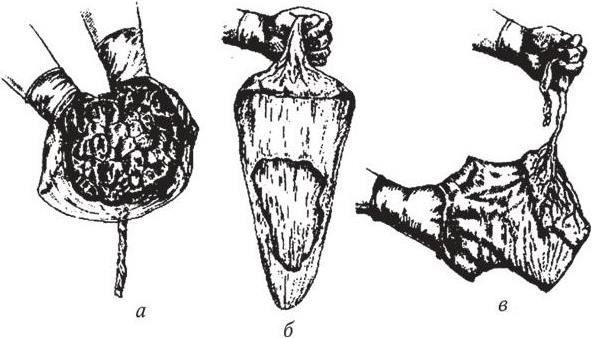

Медицинская визуализация: Признак Кюстнера-Чукалова